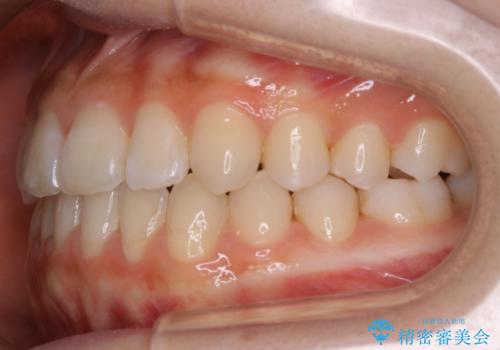

【非抜歯】受け口の改善 10代で始める本格的噛み合わせ治療

- 受け口の改善と前歯のガタつきの治療を主訴にご来院されました。

こちらの患者様の場合、上の前歯のガタつきが原因で口を閉じる際に上下の前歯の先端同士が先に当たってしまい、そこからさらに深く噛み込もうとすると下顎が前にずれていってしまうという、機能性の反対咬合であることが検査の結果わかりました。

そのため、まずは上顎の前歯のガタつきを改善していき、前歯が先に当たってしまうという症状を改善し噛み込む位置を後方の本来の位置に誘導する方法をとりました。